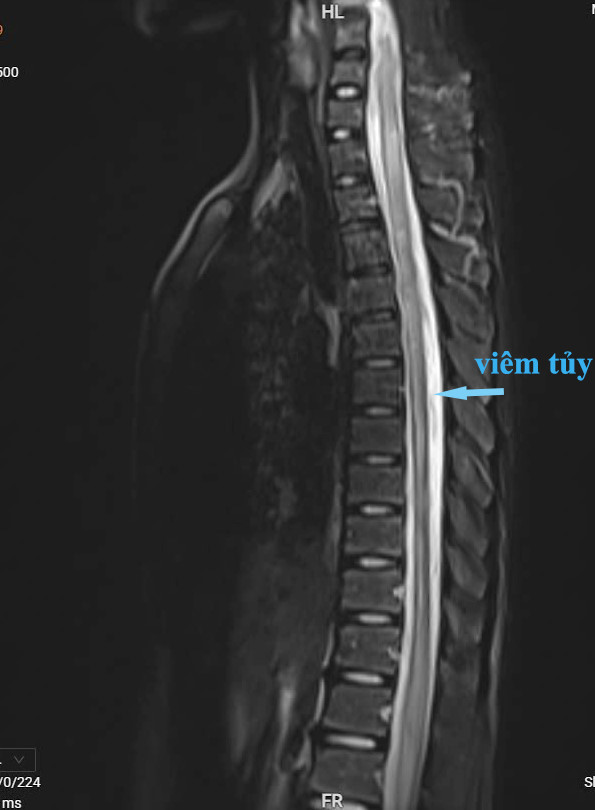

| Hình ảnh phim chụp cộng hưởng từ cho thấy người bệnh bị viêm tủy từ cột sống C3 đến D7 - Ảnh BSCC |

Người bệnh nhập viện trong tình trạng tỉnh, không sốt, liệt hai chi dưới, cơ lực 2/5. Rối loạn cảm giác từ ngang mức cột sống D10 xuống hai chân, kèm theo bí tiểu. Nhận thấy tình trạng nghiêm trọng, các bác sĩ đã tiến hành chọc dịch não tủy và chụp cộng hưởng từ cột sống có thuốc, làm điện cơ, kết quả chẩn đoán xác định người bệnh mắc viêm tủy ngang từ đốt sống C3 đến D7.